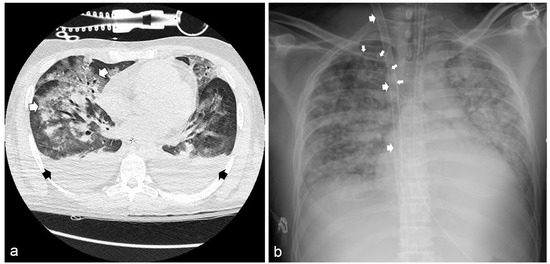

Chest X-ray and chest computed tomography (CT) scans showed bilateral pneumonia with ground-glass infiltrates (Figure 2a). Clinical and laboratory findings were consistent with the diagnosis of septic shock with multi-organ failure (MOF). Hemodynamic stability was restored through high-dose norepinephrine (up to 1.9 μg/kg/min). A broad-spectrum antibiotic therapy was also started (ceftazidime 4 g/day and meropenem 2 g/day). Nevertheless, a progressive, severe deterioration of respiratory functions was observed. Thirty-six hours after ED admission, the partial pressure of oxygen to fraction of inspired oxygen ratio (PaO2/FiO2) fell to 51.5, despite volume-controlled ventilation (FiO2 = 1; PEEP = 7 cm H2O; respiratory rate = 20 breaths/min; tidal volume = 500 mL); therefore, the ECMO team was immediately alerted, and the patient was admitted to the cardiac surgery ICU.

Figure 2.

(a) Chest computed tomography showing bilateral pleural effusion (black arrows) and diffuse ground-glass infiltrates (white arrows). (b) Chest radiography showing the bi-caval dual-lumen catheter placed in the right jugular vein (large arrows) and the central venous catheter in the right subclavian vein (small arrows).

After placing an Avalon Elite® Bi-Caval Dual-Lumen Catheter through the right internal jugular vein under trans-esophageal ultrasound guidance, a veno-venous ECMO (VV-ECMO) was started. A further triluminal central catheter was positioned through the right subclavian vein for hemodynamic and oxyphoretic monitoring and drug administration (Figure 2b).